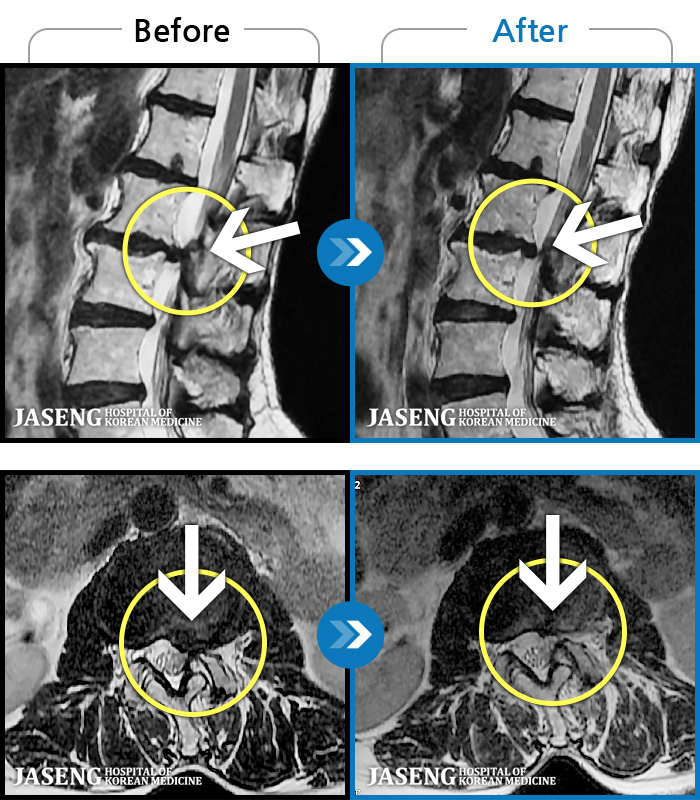

ȯںп Ǹ ǿ ԿǾ, ο ġ ۿ Ƿ ġḦ Ͻñ ٶϴ.